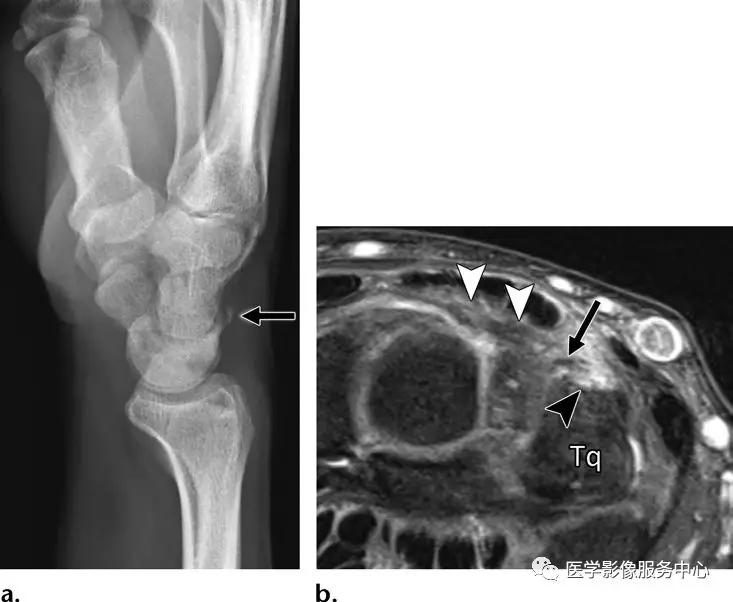

背侧三角骨骨折:

(左)在三角骨水平的背侧腕关节软组织内可见小撕脱骨片影。(右)腕骨间背侧韧带(白色箭头)从其在背侧三角骨(Tq)连接处(黑色箭头)的撕脱骨折(黑色长剪头)。